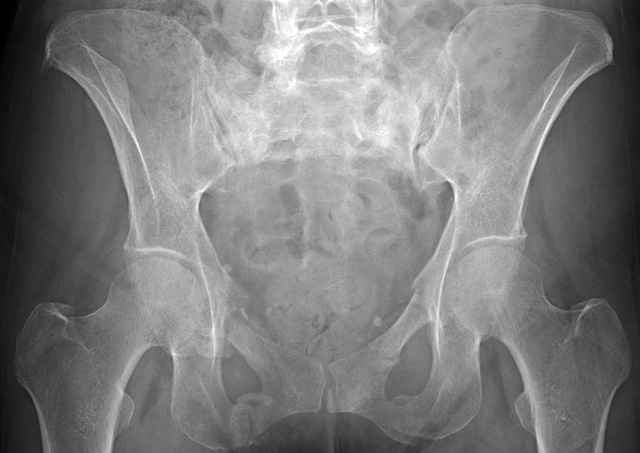

Here are a recent patient’s example slides...

3 Months After Fall

Continued Pain & Immobility

(+) Instability to Compressive Manual Exam

Pelvic CT Scan - 3 Months After Fall

Sacral Injuries

Ramus Fractures

Percutaneous Fixation

(B) Ramus-Retrograde

2 TransIliac-TransSacral

Upper Segment